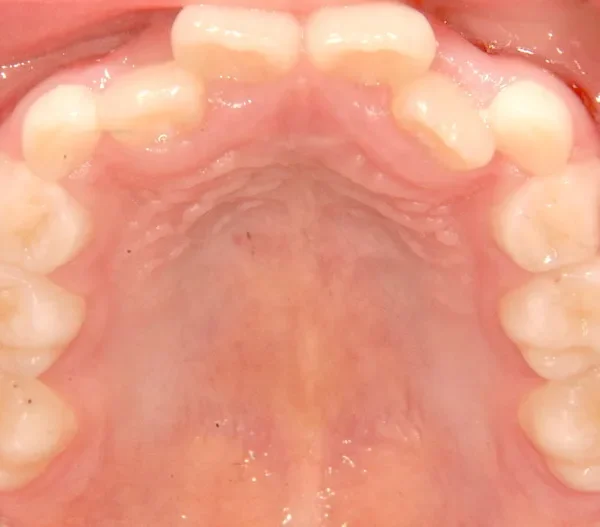

状態 永久歯が生える隙間がない(叢生)

上の歯も下の歯も歯が生えるスペースが少ない為ガタガタしています。

まずは装置で歯のアーチを広げ、歯の生えるスペースを作り、中に入ってる上の前歯を外に押し出して正常な噛み合わせにします。